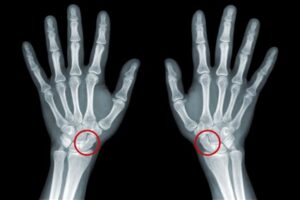

Fraturas que não cicatrizam (Pseudoartrose)

Fraturas fazem parte da vida de muitas pessoas. Seja por acidentes de trânsito, quedas, esportes de impacto ou até por doenças que enfraquecem os ossos,